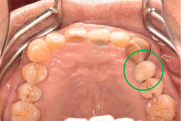

右上2本(第1第2小臼歯)の虫歯を治したい。

レントゲンで詳しく診てみると、虫歯が歯根のほうまで進行し、保存することができないことがわかり、抜歯しました。抜歯後、骨が大きく欠損していましたので、骨造成を行いインプラントを2本埋入しました。

所感

抜歯後の欠損したところを補う方法には、部分入れ歯、ブリッジ、インプラントがあることを説明したところ、自分の歯と同じような感覚で嚙むことができるインプラントを選択されました。この方は、2016年に右下にインプラント治療をし、インプラントの良さを十分に理解しておられましたので、今回も2本歯を失ったところにインプラント治療を希望されました。今回もX-Guideを使った埋入で、安心安全に行うことできました。

Before

【抜歯後】

After